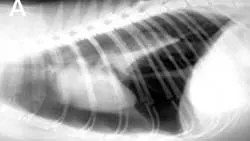

FIGURE 1

Pneumothorax is evident in this thoracic radiograph of a cat (A), as the cardiac silhouette is elevated from the sternum on the lateral projection and the lung lobes are collapsed. Close-up of the lateral view (B) shows air between the sternum and cardiac silhouette. In my experience, the lateral view is more sensitive for detecting pneumothorax because the elevation of the heart from the sternum is easily appreciated. When viewed from dorsoventral (DV) or ventrodorsal (VD) positioning, the lack of blood vessels extending out to the periphery and increased lucency of the lung fields could be overlooked.